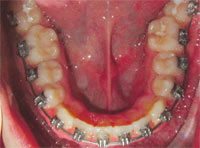

Mid-treatment Class II Correction with Forsus Vs. Ext. Upper First Bis

Should this doc extract the upper first bis and finish Class II molar? What do you think?